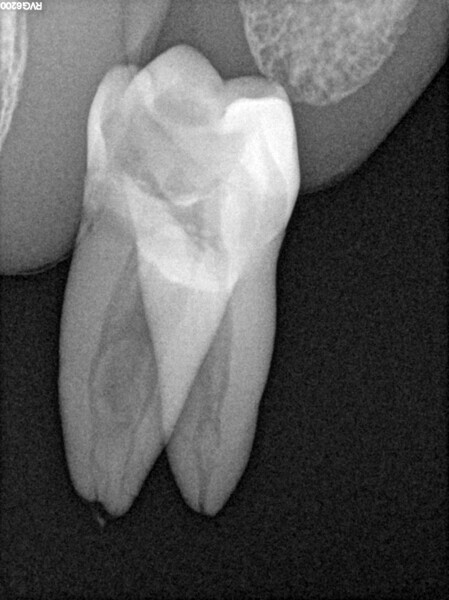

Case 2 (Figs. 27–36)

A 25-year-old female patient presented to the office owing to constant pain related to the mandibular left first molar. Pulp necrosis was diagnosed. After the emergency appointment, the patient was referred for complete treatment. The tooth was treated in the same manner as described in the previous paragraphs. After creation of the access cavity, the orifices were located. In the root chamber, the orifices of the MB, mesiolingual, DB, distomesial and distolingual canals were present. After pre-flaring and preparation of the middle third, the LPE enhanced irrigation protocol with the SkyPulse laser was performed. After the irrigation protocol in the mesial root, the irrigants started to flow between lingual and buccal canals. Such an observation suggested to the operator that some space in the isthmus had been created. It is worth mentioning that at this stage apical enlargement was not performed. Final preparation of all five canals was performed with the reciprocating file, and the final irrigation protocol was performed as in the previous case. The radiograph clearly revealed that the isthmus space was filled with the sealer. The radiograph and CBCT image revealed that there were four portals of exit in the mesial root.